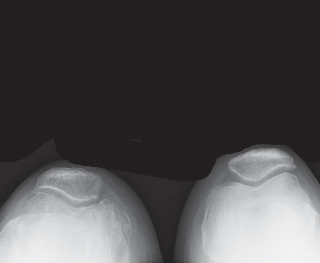

High-quality, standardized, weight-bearing radiographs are the cornerstone of preoperative planning. A standard knee series must include a weight-bearing anteroposterior (AP) view, a weight-bearing lateral view in extension, and a skyline (Merchant) view of the patella. The AP view reveals joint space narrowing, subchondral sclerosis, osteophyte formation, and the presence of subchondral cysts. The lateral view is essential for assessing patellar height (Insall-Salvati ratio) and the posterior slope of the tibia.

Crucially, we must obtain a 45-degree posteroanterior (PA) weight-bearing view (the Rosenberg view). Because cartilage wear in early-to-moderate OA predominantly affects the posterior aspect of the femoral condyles, the standard extension AP view may falsely appear normal. The flexed Rosenberg view unloads the patella and brings the worn posterior condyles into contact with the tibia, revealing hidden joint space narrowing. Furthermore, a full-length, hip-to-ankle standing radiograph is highly recommended, particularly in patients with severe deformities or a history of prior femoral/tibial fractures, to accurately determine the mechanical axis and identify any extra-articular deformities that might complicate intramedullary instrumentation.